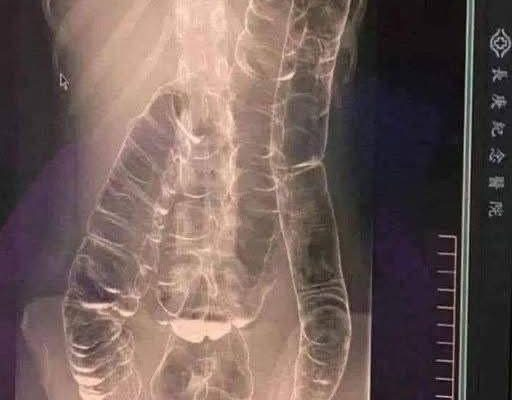

In some rare cases, chronic constipation can evolve into a medical emergency. A condition known as toxic megacolon occurs when the colon becomes severely distended due to a prolonged buildup of stool and gas. The colon loses its natural ability to contract and move waste through the intestines, leading to bloating, intense discomfort, and in severe cases, systemic infection or tissue damage.

While toxic megacolon is more commonly associated with inflammatory bowel diseases like ulcerative colitis or Crohn’s disease, extreme cases of untreated constipation can also trigger similar symptoms.

When stool accumulates, the colon stretches beyond its normal limits. Over time, this can weaken the muscular wall of the intestines and impair their ability to contract. The result is a cycle of worsening constipation and increased discomfort.